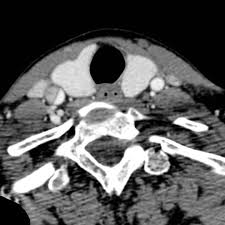

The inside of the artery is covered with a thin layer of cells called intima — it is like a skin. Blood in the separated layers of the vessel wall can lead to blood clot formation. Occur secondary to carotid artery dissections. Carotid artery dissection has been described after chiropractic manipulation. The extracranial portion of the internal carotid artery is much more frequently involved than the intracranial portion.

Blood in the separated layers of the vessel wall can lead to blood clot formation. A carotid dissection is a tear in the artery wall that allows blood to flow between the wall layers. It can manifest as headache (the most common early symptom (3)) with or. The tear may cause stenosis, an irregular narrowing of the opening in the vessel, and occlusion, a flap of the vessel wall protruding into the opening. Blood leaks out through this gap and spreads between the layers of the wall. Advertising on our site helps support our mission. Commonest in those in their mid 40s but seen at any age. Blood vessel walls normally have three layers, and a tear in any of these can allow blood to flow into the resulting space, causing the vessel to bulge.

Abstract traumatic carotid artery dissections are uncommon and potentially devastating injuries that often have a delayed presentation. Carotid dissection is a breakdown of the layers of the carotid artery that causes the wall to tear. It can cause problems in several ways. In regards to risk of artery dissection with activity, we know that some activities are associated with artery dissection more than others. Carotid dissection is about 3 times commoner than vertebral.